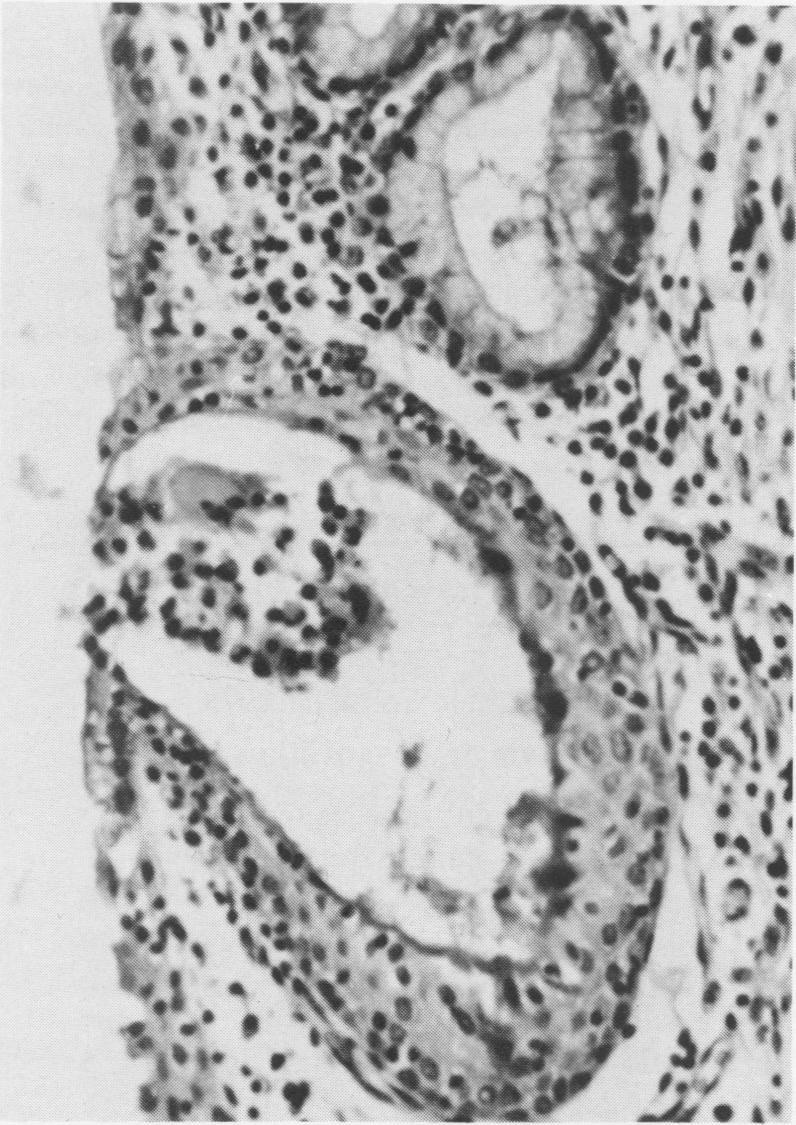

A granular vulvitis syndrome associated with ureaplasma infection was first recognized in Ontario dairy herds in 1972. The acute form of the disease was characterized by a purulent vulvar discharge, an inflamed hyperemic vulvar mucosa and varying degrees of granularity. In the chronic form, there was an absence of a purulent discharge and a gradual decline in the severity of the hyperemia and granularity. Epithelial inclusion cysts were observed in the vulvar epithelium of approximately 10% of affected cows.A seasonal variation in the incidence of the disease was observed. Herd morbidities during the summer months reached a low of 37% and increased to 75% during the winter months with constant housing.When widespread in herds, the acute form of the disease had a significant effect on fertility. In four herds examined, first service conceptions dropped on average by 27%. The chronic form of the disease had a less detrimental effect on fertility with first service conceptions being reduced on average by 13%. Intrauterine infusions of a tetracycline 24 hours postbreeding were found to be of value in improving conception rates in acutely affected herds.

1972年,在安大略省的奶牛群中首次发现了一种与脲原体感染相关的颗粒性外阴炎综合征。该疾病的急性形式表现为脓性外阴分泌物、外阴黏膜充血发炎以及不同程度的颗粒状。慢性形式则表现为无脓性分泌物,充血和颗粒状的严重程度逐渐下降。在约10%的患病奶牛的外阴上皮中观察到上皮包涵体囊肿。观察到该疾病的发病率存在季节性变化。夏季牛群发病率低至37%,冬季持续圈养时升至75%。当该病在牛群中广泛传播时,急性形式对繁殖力有显著影响。在检查的四个牛群中,首次配种受孕率平均下降了27%。慢性形式对繁殖力的不利影响较小,首次配种受孕率平均降低13%。发现在配种后24小时进行宫内四环素灌注对提高急性感染牛群的受孕率有价值。